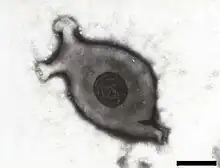

Electron micrograph of Mycoplasma gallisepticum, scale bar 140 nm | |